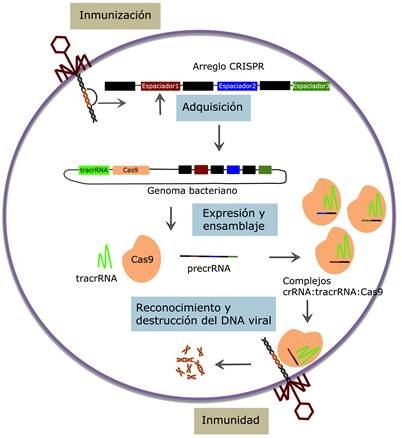

VacunaciónPrioridad preventivaLa cobertura frente a sarampión, influenza y grupos vulnerables sigue siendo clave.

InvestigaciónVacunas e IAEnsayos, vigilancia genómica y salud digital avanzan como herramientas estratégicas.